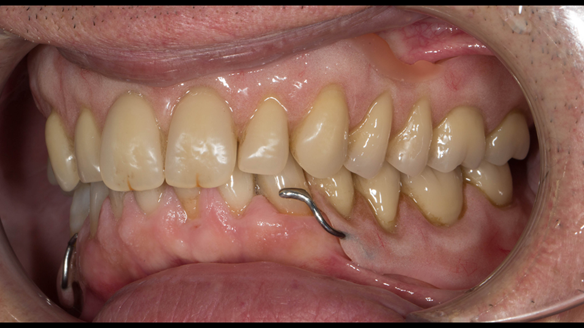

- Generalised periodontitis; stage IV grade C: currently unstable, risk factors: smoker.

- The remaining maxillary teeth had hopeless prognosis in the short term. They exhibited 80 - 100% alveolar bone loss with increased mobility (Grade 2 - 3).

- The lower right second premolar and lower left first premolar (LR5 LL4) had hopeless prognosis in the short term. They exhibited 80 - 100% alveolar bone loss with grade 3 mobility.

- The remaining mandibular teeth had approximately 30 - 50% alveolar bone loss with grade 1 mobility.

The clinical situation and treatment process is shown in detail below with photographs.